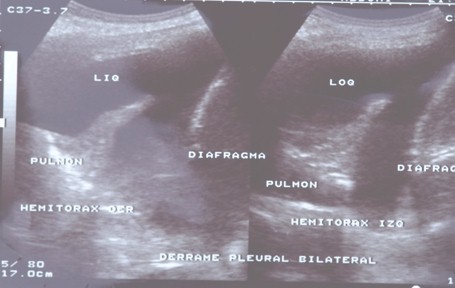

ECOGRAFÍA

Confirma el diagnóstico a los pies de la cama del paciente

Orienta la naturaleza del derrame (homogeneidad, loculaciones, tabiques)

Guía la toracocentesis minimizando riesgos